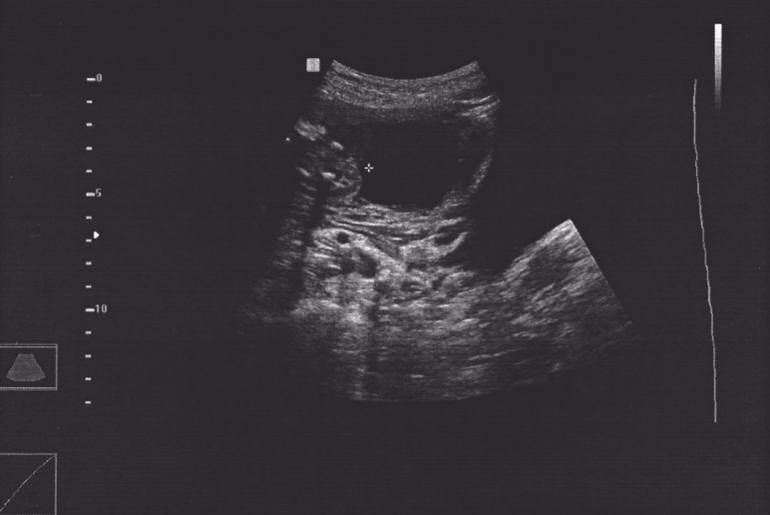

Пол малышаВообщем хочу поделится своей историей. Почему-то всю жизнь думала, что у меня будет сын. Все друзья и родственники тоже хором твердили, что видят меня мамой мальчика. В начале беременности я сама ходила с полной уверенностью в этом. Когда пришла на первый скрининг, а было это почти в 14 недель (то есть рассмотреть пол теоретически было можно с довольно большой вероятностью) и узистка мне сказала, что 90% процентов, что это мальчик, я совершенно не удивилась и уже окончательно настроилась на голубенькие одежки и воспитание "настоящего мужчины":). Хотя, признаться честно, всегда мечтала о бантиках и куклах. Каково же было мое удивление, когда я попала на узи в 20 недель и та же врач мне сказала: "У вас девочка, сомнений быть не может." Записала все данные в протокол и отправила меня восвояси с идиотской улыбкой на лице. Я была несказанно счастлива, но сомнения не давали покоя, особенно учитывая 90-то процентную уверенность этого же врача в первый раз. Не вытерпев и двух дней я записалась в платную клинику к другому специалисту, тем более в ЖК мне не сделали ни одной фотографии (почему-то я думала, что сделать скриншот и скинуть на флешку картинку можно с любого аппарата). И таки да, это девочка! Вот такая история.